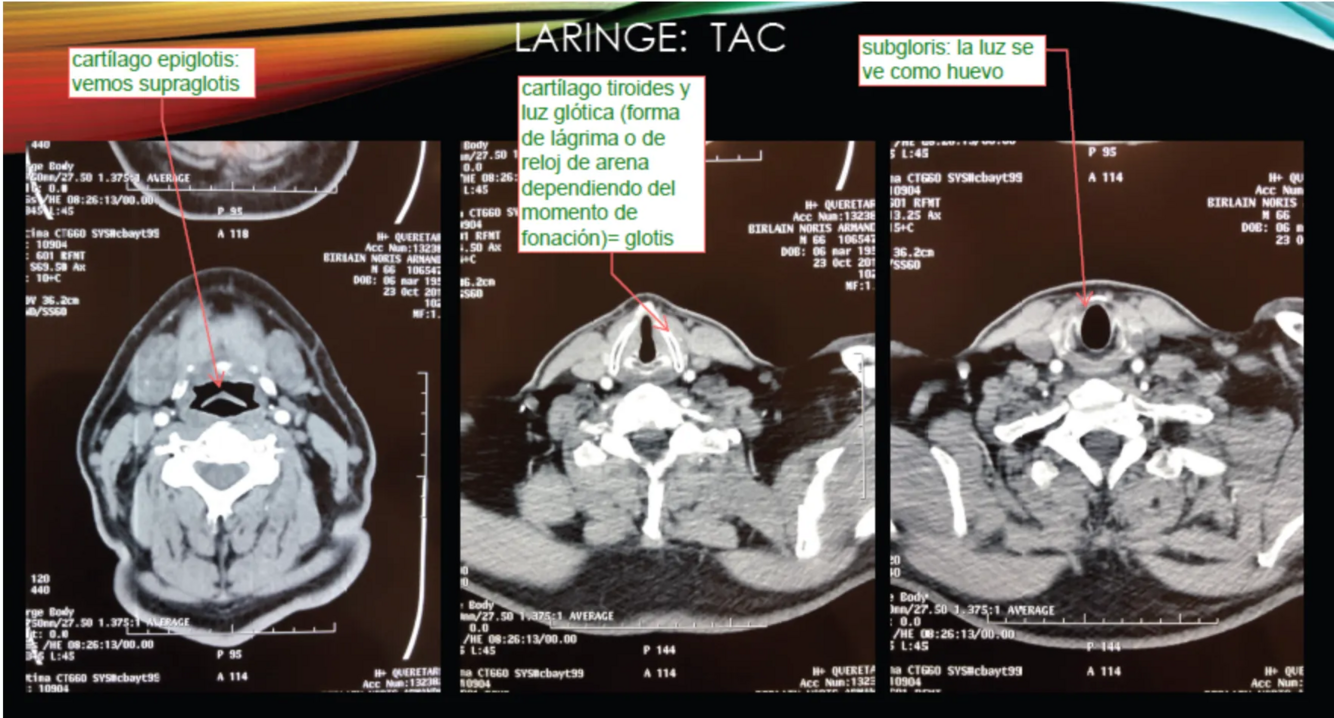

¿Qué hallazgos pueden verse en TAC laríngeo?

A

• A nivel glótico: tejido blando normal o patológico

• Cartílagos calcificados

• Estenosis esofágica